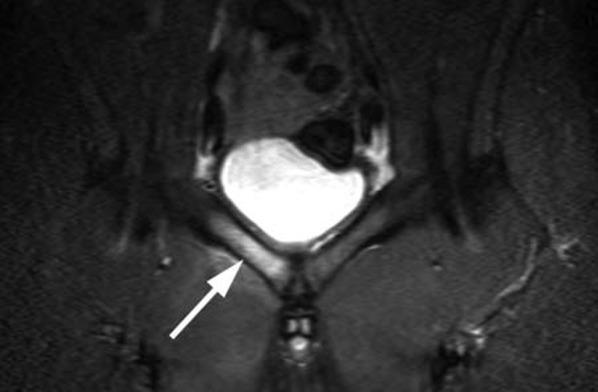

Orthopaedic magnetic resonance imaging challenge: apophyseal avulsions at the pelvis.

Apophyseal avulsion injuries of the hip and pelvis are frequent athletic injuries in children and adolescents, most commonly associated with explosive movement or sprinting. This article details typically encountered apophyseal injuries and their appearance on magnetic resonance imaging.